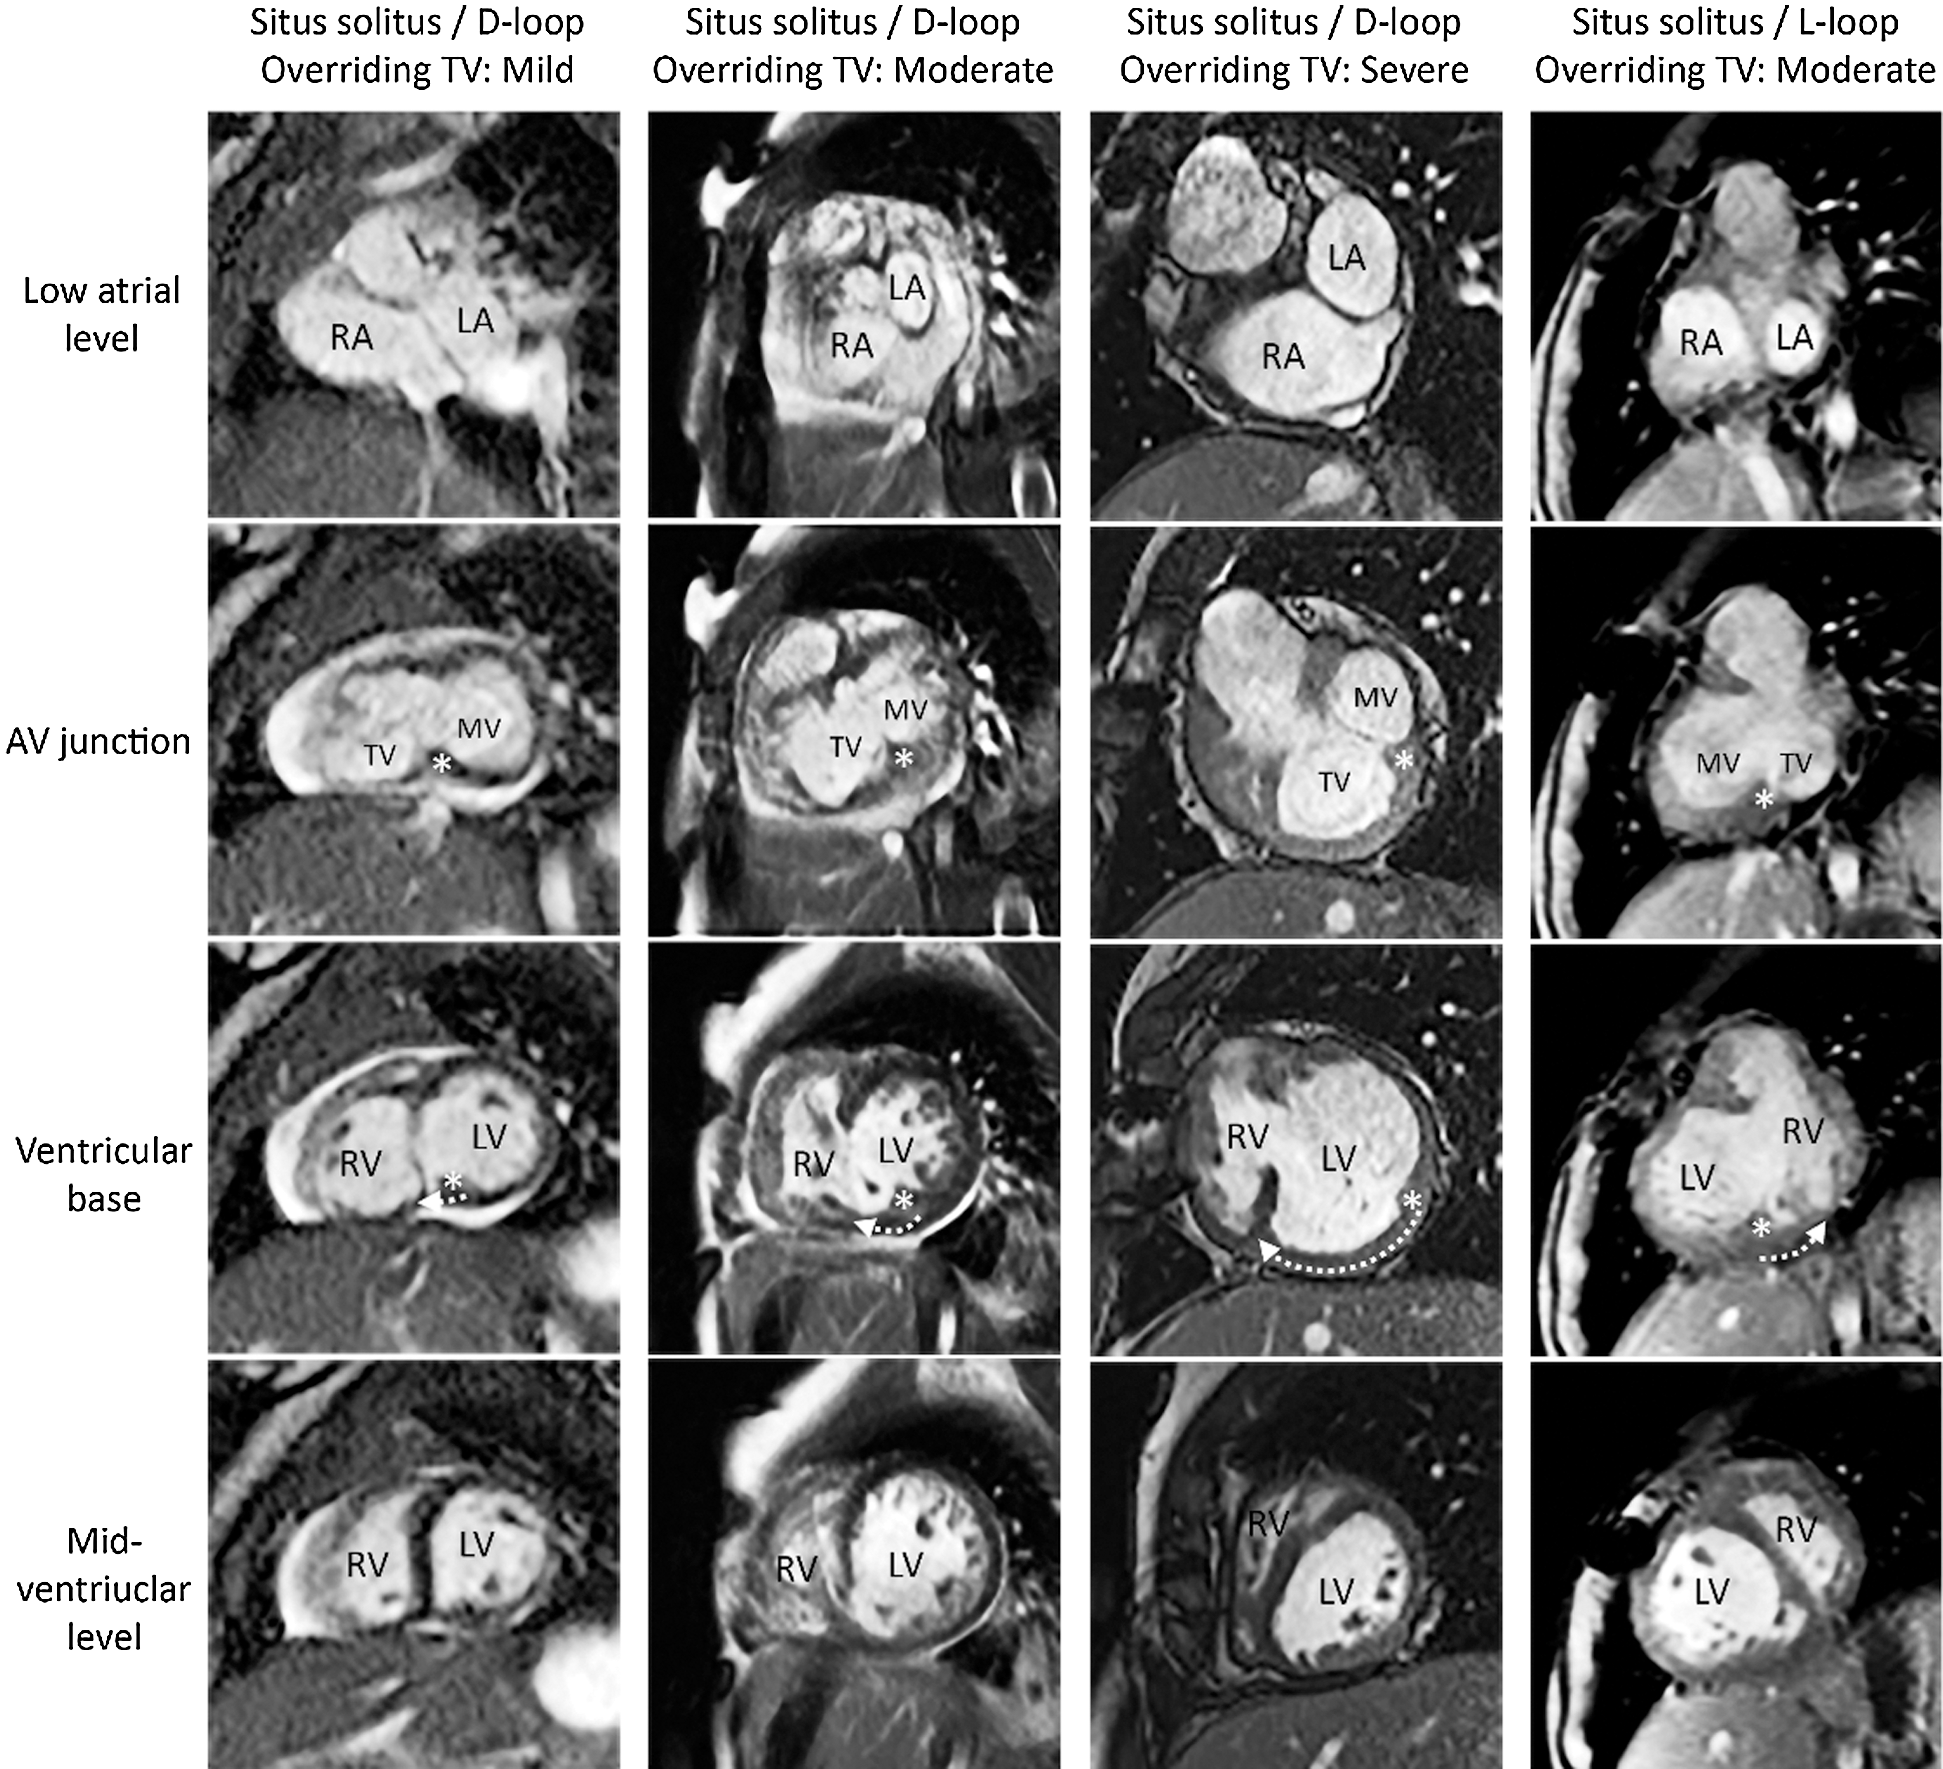

Figure 2: Short-axis MR images from 4 patients with overriding/straddling tricuspid valve. Three panels on the left show the cases with various severity of overriding in the setting of situs solitus and D-loop ventricles. Right hand panel shows the case occurring in the setting of situs solitus and L-loop ventricles. The location of the crux cordis/posteromedian muscle ridge is marked with an asterisk. The direction and degree of the malalignment is marked with a curved arrow in the third row figures. Note the increasing separation of the two structures with increasing severity of overriding. AV, atrioventricular; LA, left atrium; LV, left ventricle; MV, mitral valve; RA, right atrium; RV, right ventricle TV, tricuspid valve

Figure 3: Short-axis MR images from 4 patients with overriding/straddling mitral valve. Three panels on the left show the cases with various severity of overriding in the setting of situs solitus and D-loop ventricles. Right hand panel shows the case occurring in the setting of situs solitus and L-loop ventricles. The location of the crux cordis is marked with an asterisk. The direction and degree of the malalignment is marked with a curved arrow in the second row figures. The ventricular septum inserts to the posterior interventricular groove that is aligned with the crux cordis. The anterior interventricular groove is deviated toward the side of the left ventricle in relation to the atrial septal plane in all cases. AV, atrioventricular; LA, left atrium; LV, left ventricle; MV, mitral valve; RA, right atrium; RV, right ventricle TV, tricuspid valve